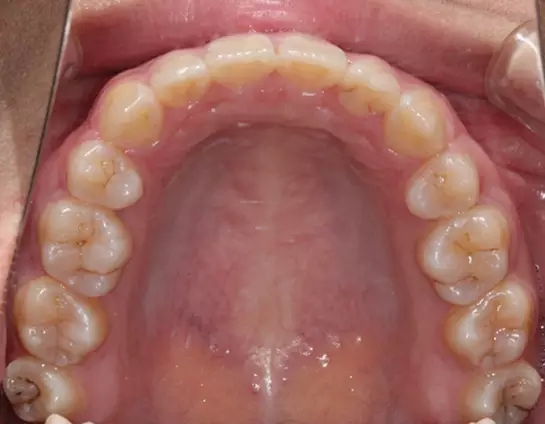

Damon 病例分享:安氏 II 類(lèi)二分類(lèi)露齦笑的矯治(董一磊)

患者信息